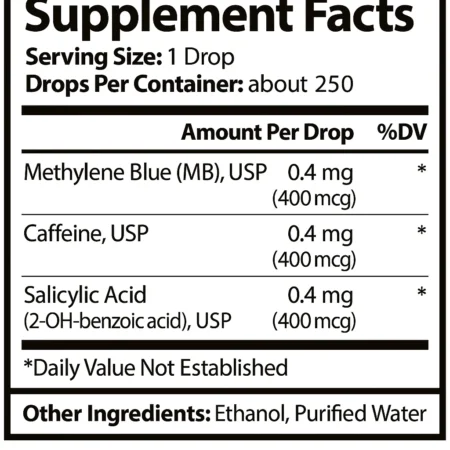

Oxidal Blue - Sănătate mitocondrială / oxigenare / întinerire

Evaluat la 5.00 din 527.10€ -